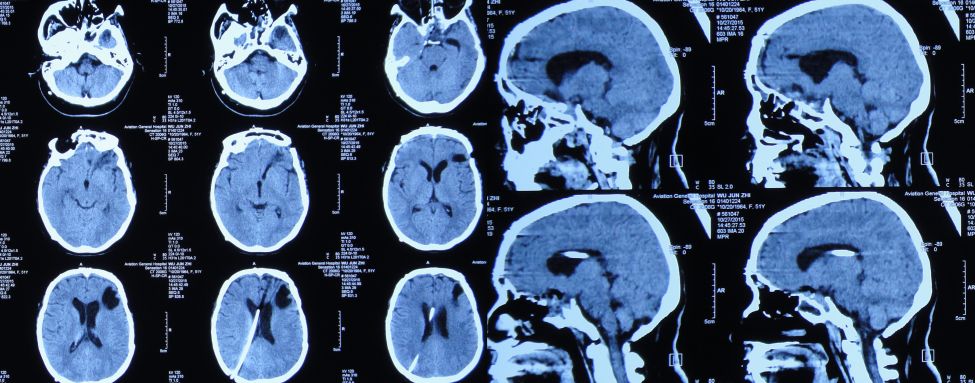

患者女,50岁,安徽省淮北市人。2014年12月14日,患者因高处坠落伤(2米左右)伤及头胸部及四肢,致昏迷,左耳、左鼻流血性液体,急诊前往安徽省淮南市潘集区某医院急查头CT显示左额叶脑挫伤、左侧颞骨凹陷性骨折、脑肿胀、颅内积气(图1);眼眶CT显示双侧眼眶内侧壁骨折(图2);胸部CT显示左侧肋骨骨折伴肺挫伤;右上肢X片显示右桡骨远端粉碎性骨折;左肩部X片显示左侧锁骨骨折。立即给予住院,保守治疗。

图1:2014年12月14日头CT:左额叶脑挫伤、左侧颞骨凹陷性骨折、脑肿胀、颅内积气